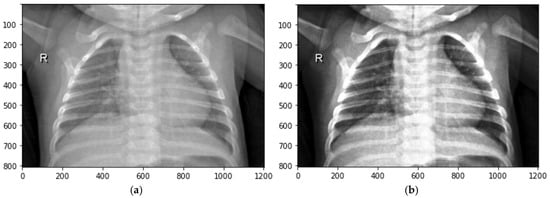

A fuzzy data augmentation algorithm is proposed to improve the image quality in the fuzzy logic process. This algorithm includes an advanced mathematical approach to determine the membership function, optimizing the fuzzy logic process. The resulting fuzzy-transformed images are a specialized dataset designed for training CNN. The image enhancement algorithm consists of 12 steps and is illustrated in Figure 3.

Figure 3.

Image enhancement process using fuzzy techniques.